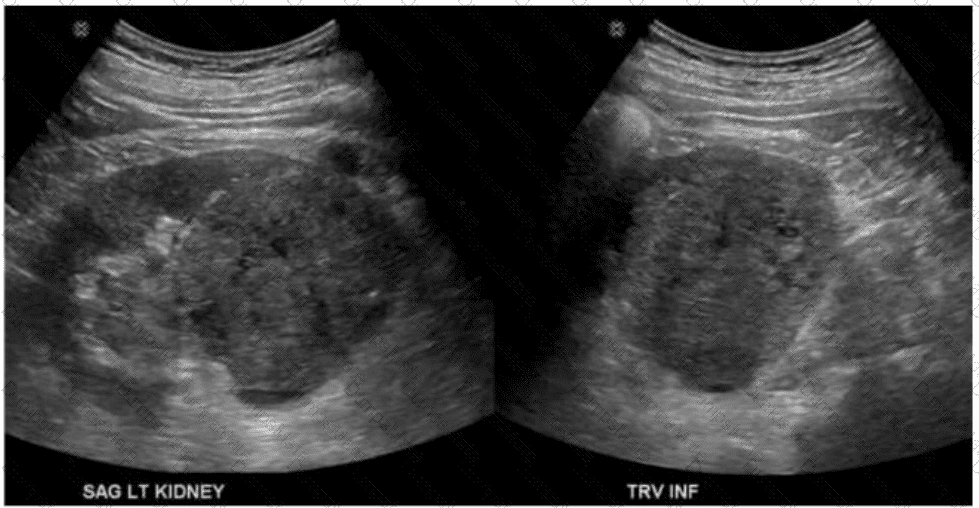

Questions 28

Which condition is most consistent with the findings in this image?

AB-Abdomen Question 28

Options:

A.

Fungal balls

B.

Renal cell carcinoma

C.

Acute pyelonephritis

D.

Medullary sponge kidney